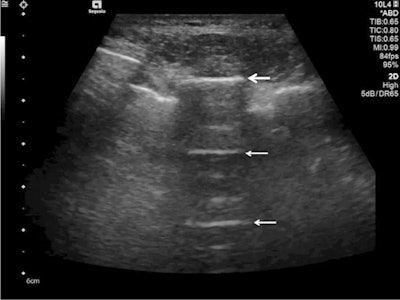

Ultrasound detected A-lines using an abdominal probe. A-lines (white arrows) appear as bright horizontal lines deep to the pleural line (bold white arrow).

Ultrasound detected A-lines using an abdominal probe. A-lines (white arrows) appear as bright horizontal lines deep to the pleural line (bold white arrow).Due to the fact that this is a classic reverberation artefact, the distance from the skin to the pleural surface equals the distance from the pleural line to the first A-line, the first A-line to the second A-line, etc. The A-profile is shaped by intact ("dry") lung parenchyma containing air when it is combined with normal lung sliding. If sliding is absent, it is intensely suggestive of a pneumothorax.